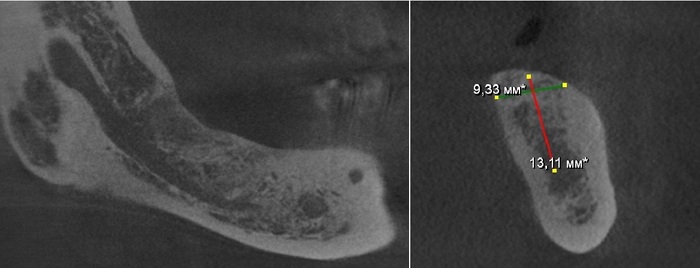

Фрагмент компьютерной томографии (вид сбоку):

Первый вопрос, который я задал, – почему не было проведено исправление прикуса до имплантации?